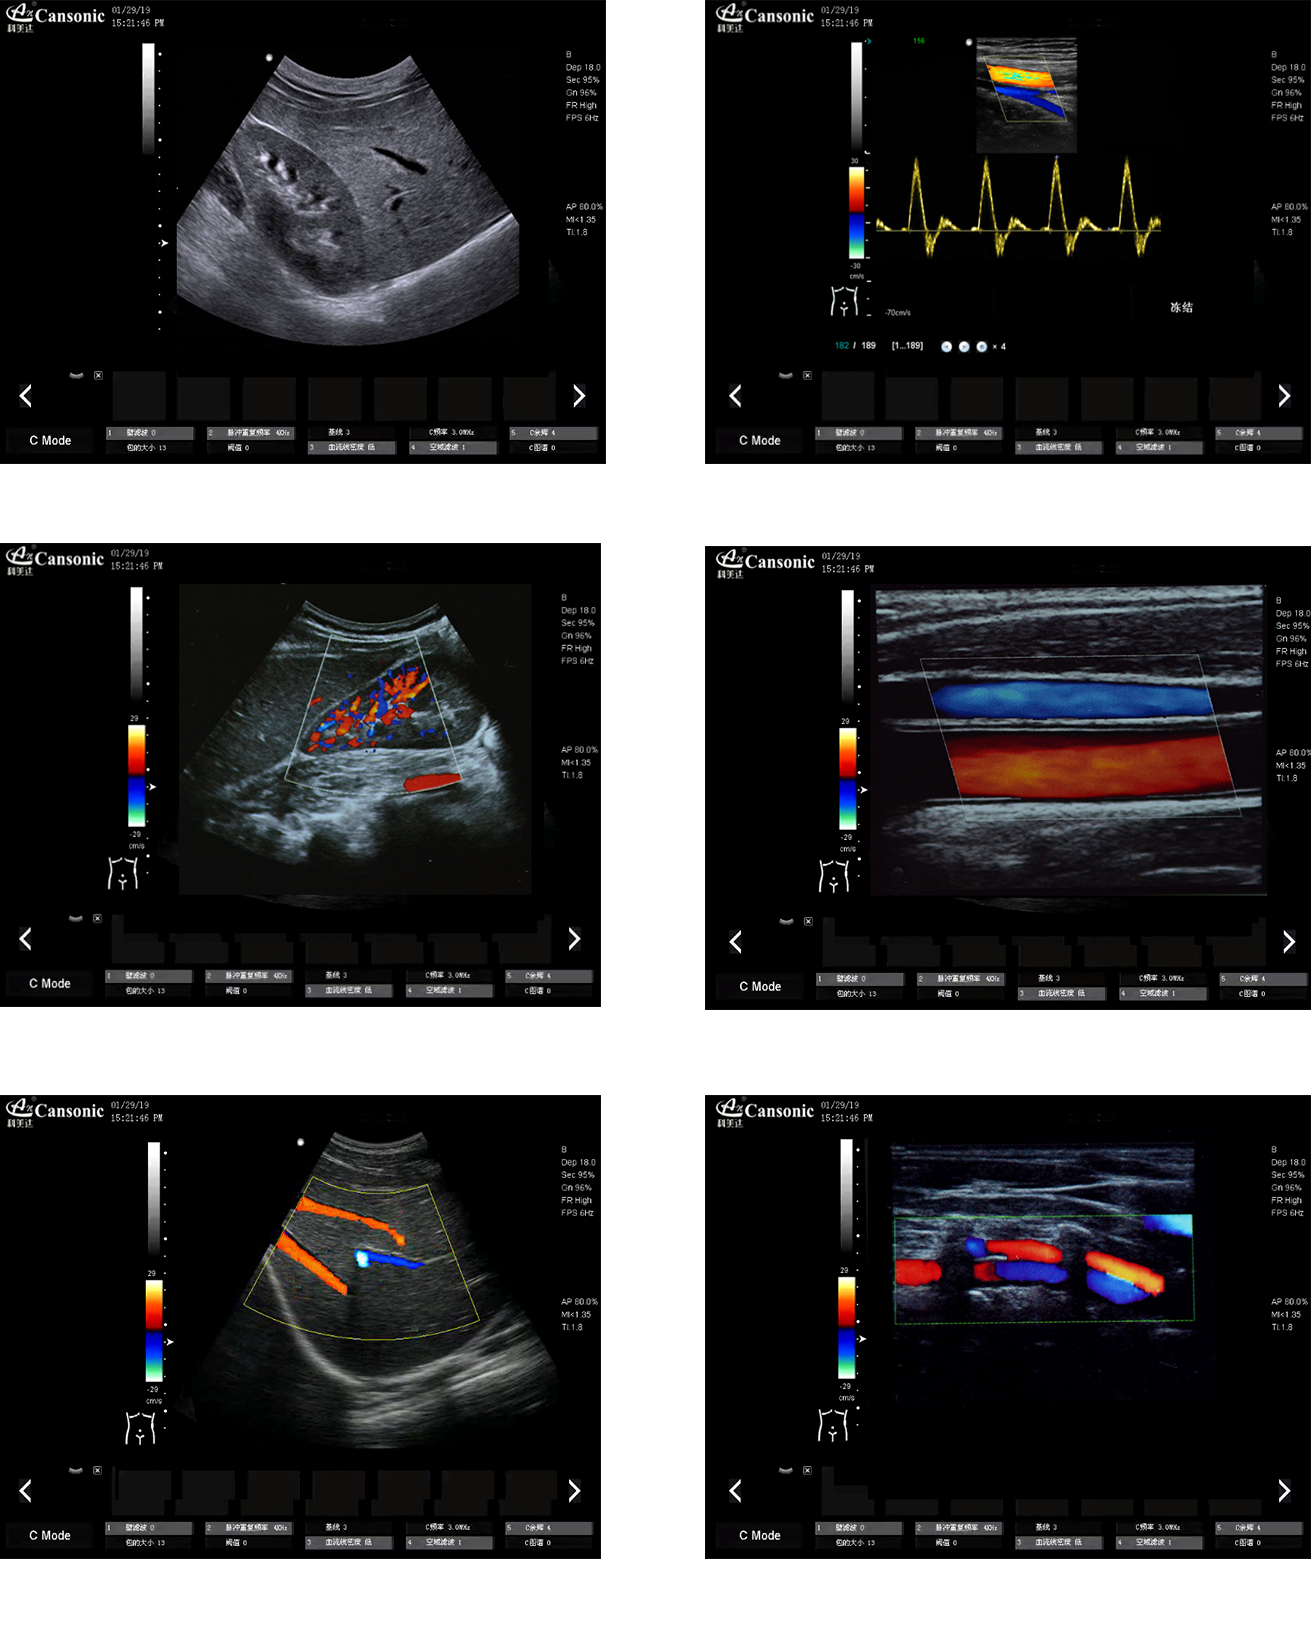

科美達K18圖像實例

1、推車式彩色多普勒全身機,擁有優異的圖像質量和突出的血流顯示效果

2、出色的組織均勻性,減少噪聲干擾,提高圖像顆粒細膩度

3、精細血流識別技術,超寬帶非線性造影成像

4、特異性組織成像結合邊緣增強技術,提供可疑病變更多的邊界信息

5、復合成像增益編碼控制技術,提升機器運算速度,無延遲實時掃查

6、自動包絡處理,實現快速診別診斷,提高醫生掃查效率